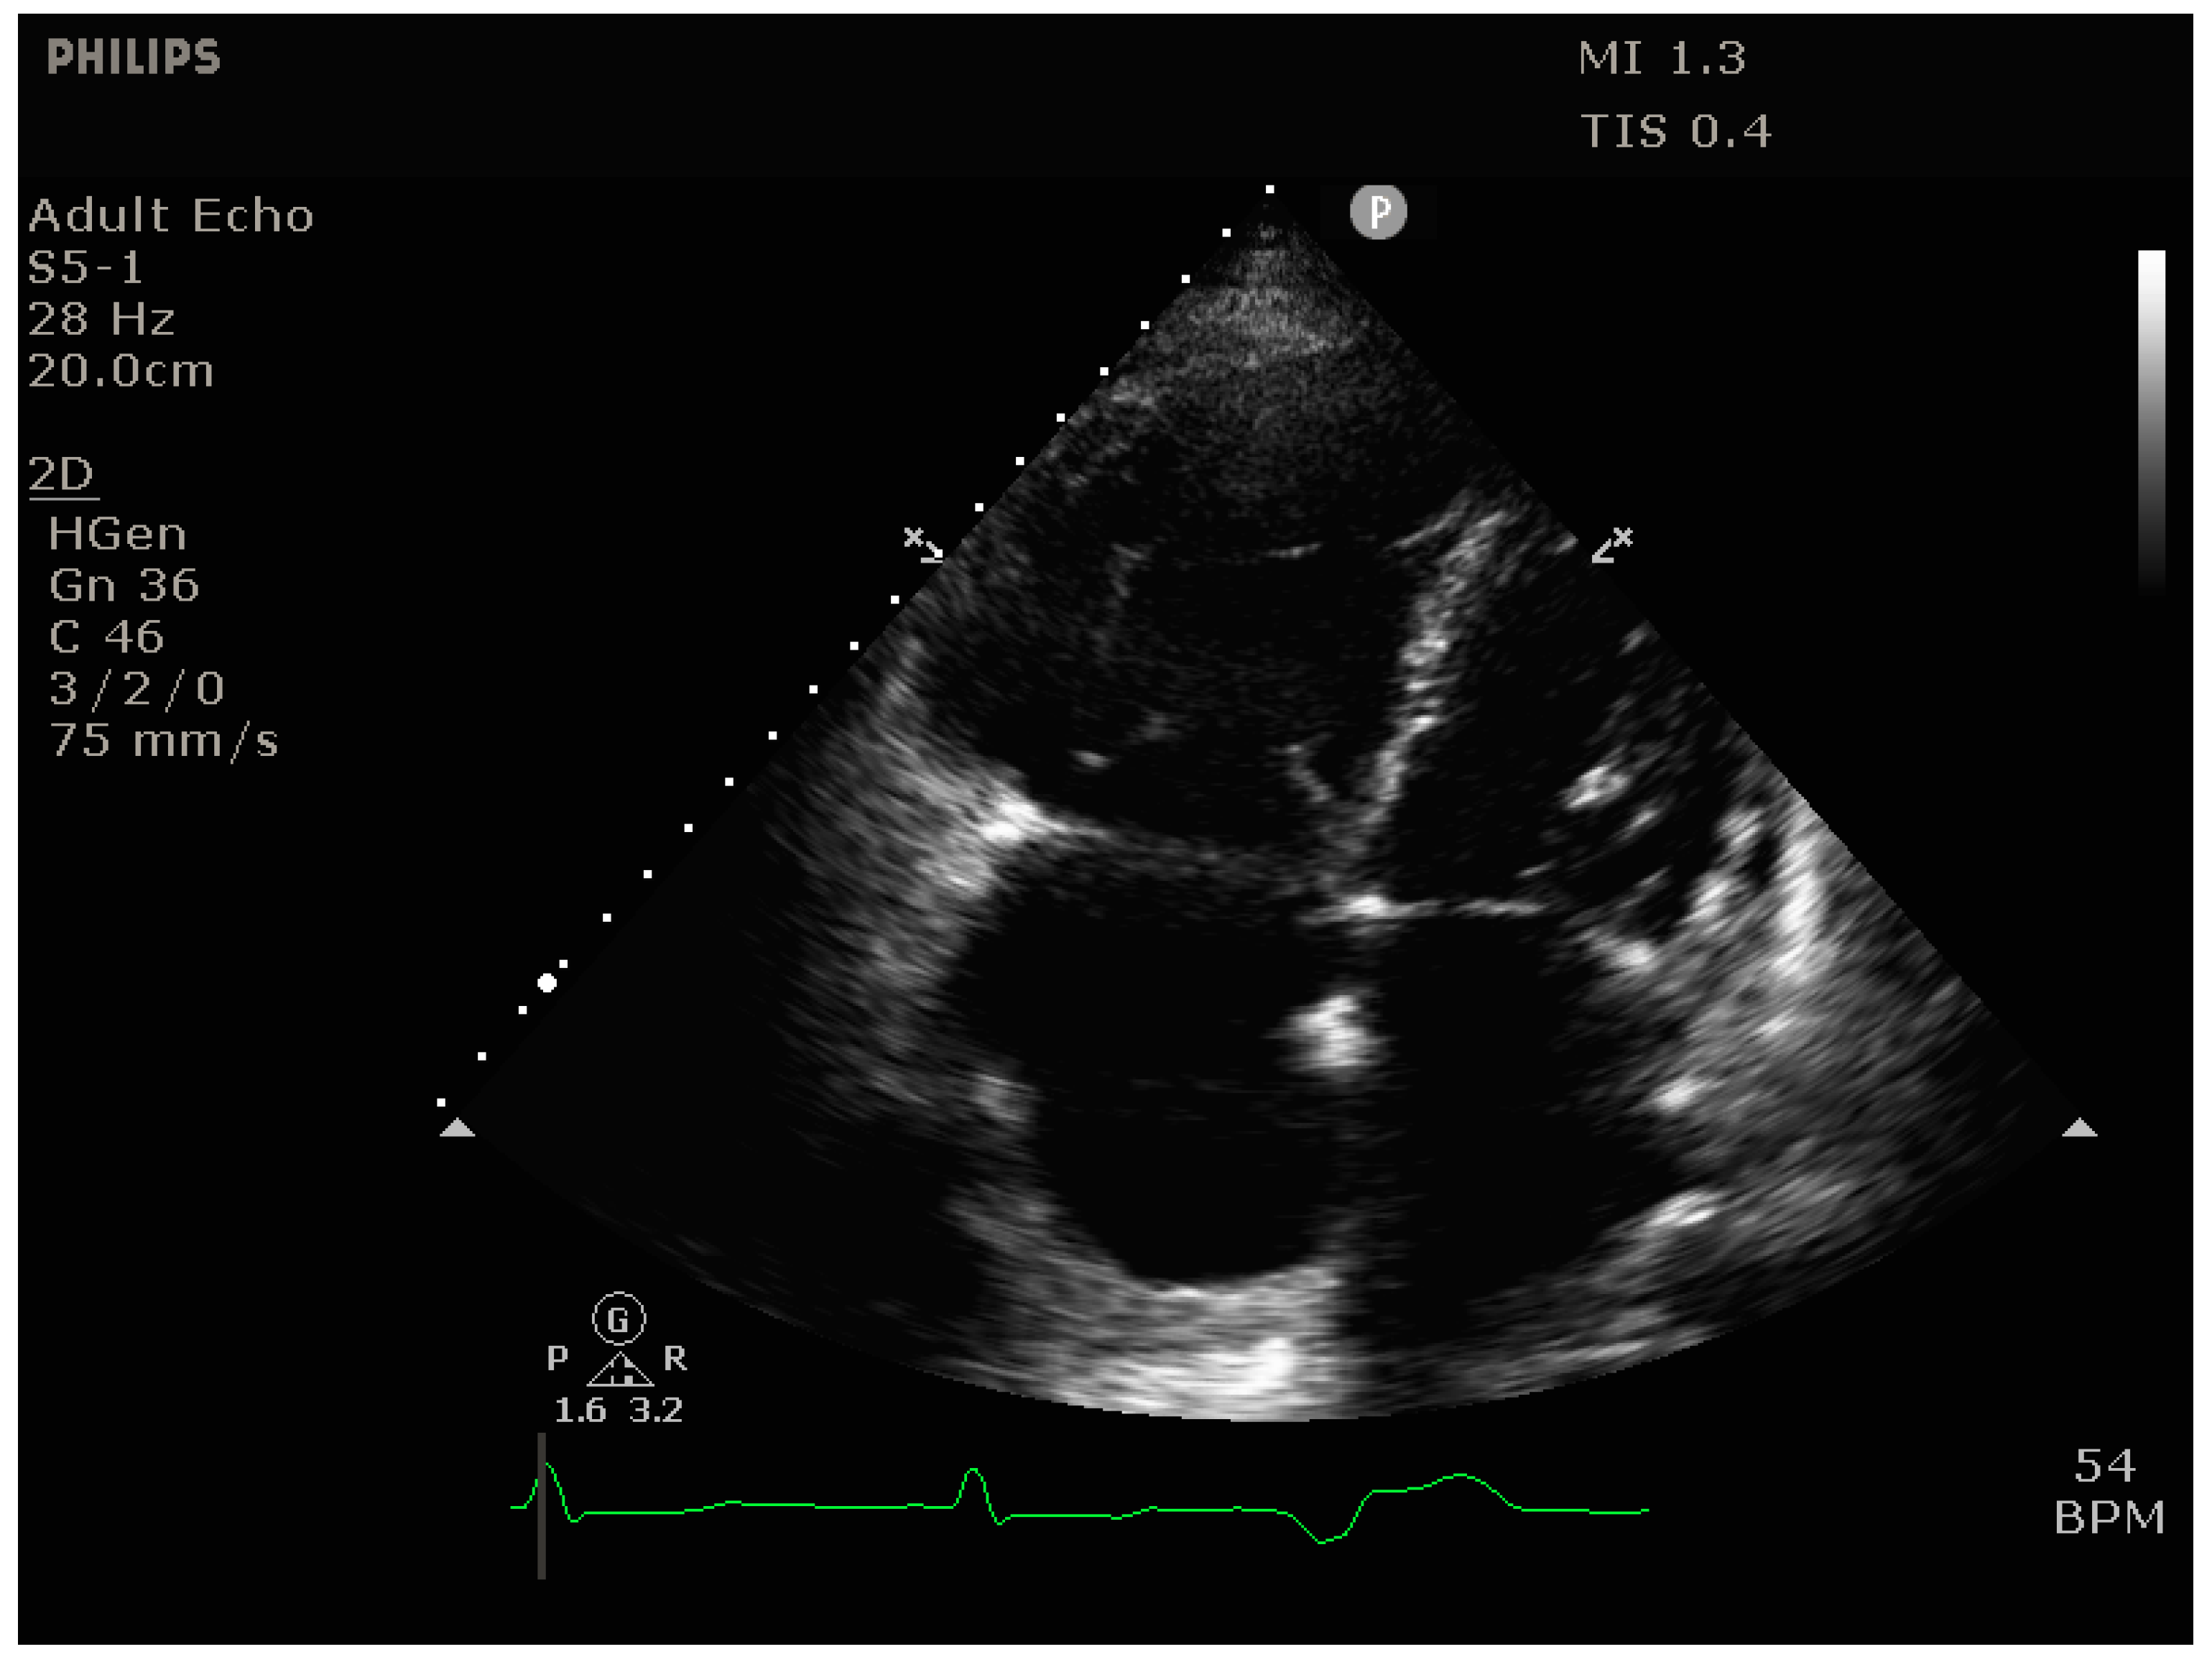

4.2.2. Echocardiography

- Signs of RV dilation: D-shaping, increased RV:LV ratio, tricuspid regurgitation

- Signs of impaired RV systolic function: reduced tricuspid annular plane systolic excursion (TAPSE)

- Signs of elevated RV preload (plethoric inferior vena cava [IVC])

- Vena contracta (VC) width: The width of the regurgitant jet is measured as it leaves the regurgitant orifice. It is best imaged perpendicular to the valve plane, e.g., in the apical 4-chamber view, using CFD with a Nyquist limit of 50–60 cm/s. The VC width corresponds to the width of the narrowest portion of the jet (the “neck), with values > 7 mm suggestive of severe TR.

- Proximal isovelocity surface area (PISA): [46] With significant TR, there is a flow acceleration proximal to the regurgitant valve orifice. This proximal flow convergence occurs along concentric hemispheres and can be visualized using CFD with an adequately set Nyquist limit (15–40 cm/s) to maximize delineation of the flow acceleration. The radius of the PISA correlates with TR severity, with values > 9 mm suggestive of severe TR.